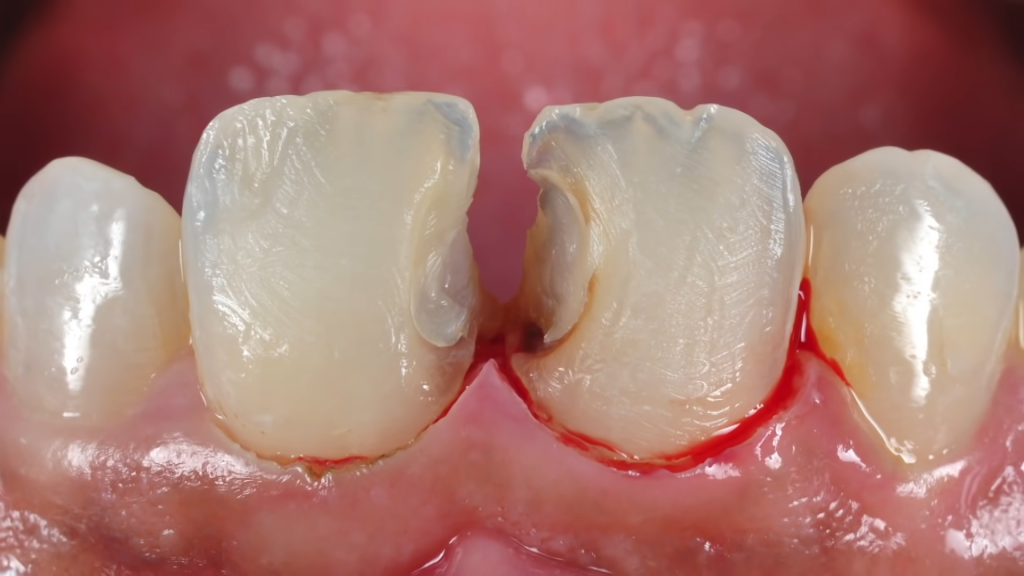

- Repair of dental injuries, including chipped, cracked, or knocked-out teeth.

- Prompt care for toothaches, infections, dental trauma, or severe decay.

- Root Canal Treatment (Baby Teeth):

- Baby teeth may require RCT if severely decayed or injured.

- Removes infection from the pulp, stabilizes the tooth, and preserves it until natural shedding.